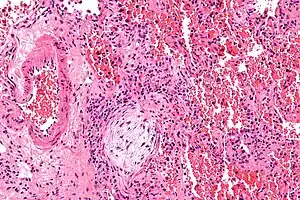

Micrograph showing a Masson body (off center left/bottom of the image – pale circular and paucicellular), as may be seen in cryptogenic organizing pneumonia. The Masson body plugs the airway. The artery associated with the obliterated airway is also seen (far left of the image). H&E stain.

Biopsy findings in patients with organizing pneumonia consist of loose connective tissue plugs involving the alveoli, alveolar ducts and bronchioles. The loose connective tissue plugs occupying the alveolar spaces often connect to other connective tissue plugs in nearby alveoli via the pores of Kohn creating a characteristic butterfly pattern on histology.[7] There is usually minimal to no interstitial inflammatory changes in biopsies of organizing pneumonia.[7]

Histologically, cryptogenic organizing pneumonia is characterized by the presence of polypoid plugs of loose organizing connective tissue (Masson bodies) within alveolar ducts, alveoli, and bronchioles.